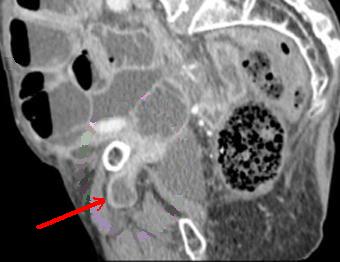

| Hernie inguinale etrangle : Image

d'engage du grele dans fossette inguinale

moyenne + image de distension de l'intestin au

dessus de l'obstacle ( fleche rouge ) . |

La TDM est tres

l'interet de presiser facilement le type de hernie :

hernie inguinale direct etrangle avec image de grele

en de dans des vaisseaux epigastriques .La TDM peut

differentiele avec les autres masses de la region

scrotale . |

| Hernie obturatrice etranglee : Image du

grele engage dans orifice interne du canal sous-

pubienne . Image CT scanner en coupe axiale . |

Meme cas en coupe TDM

sagitale |